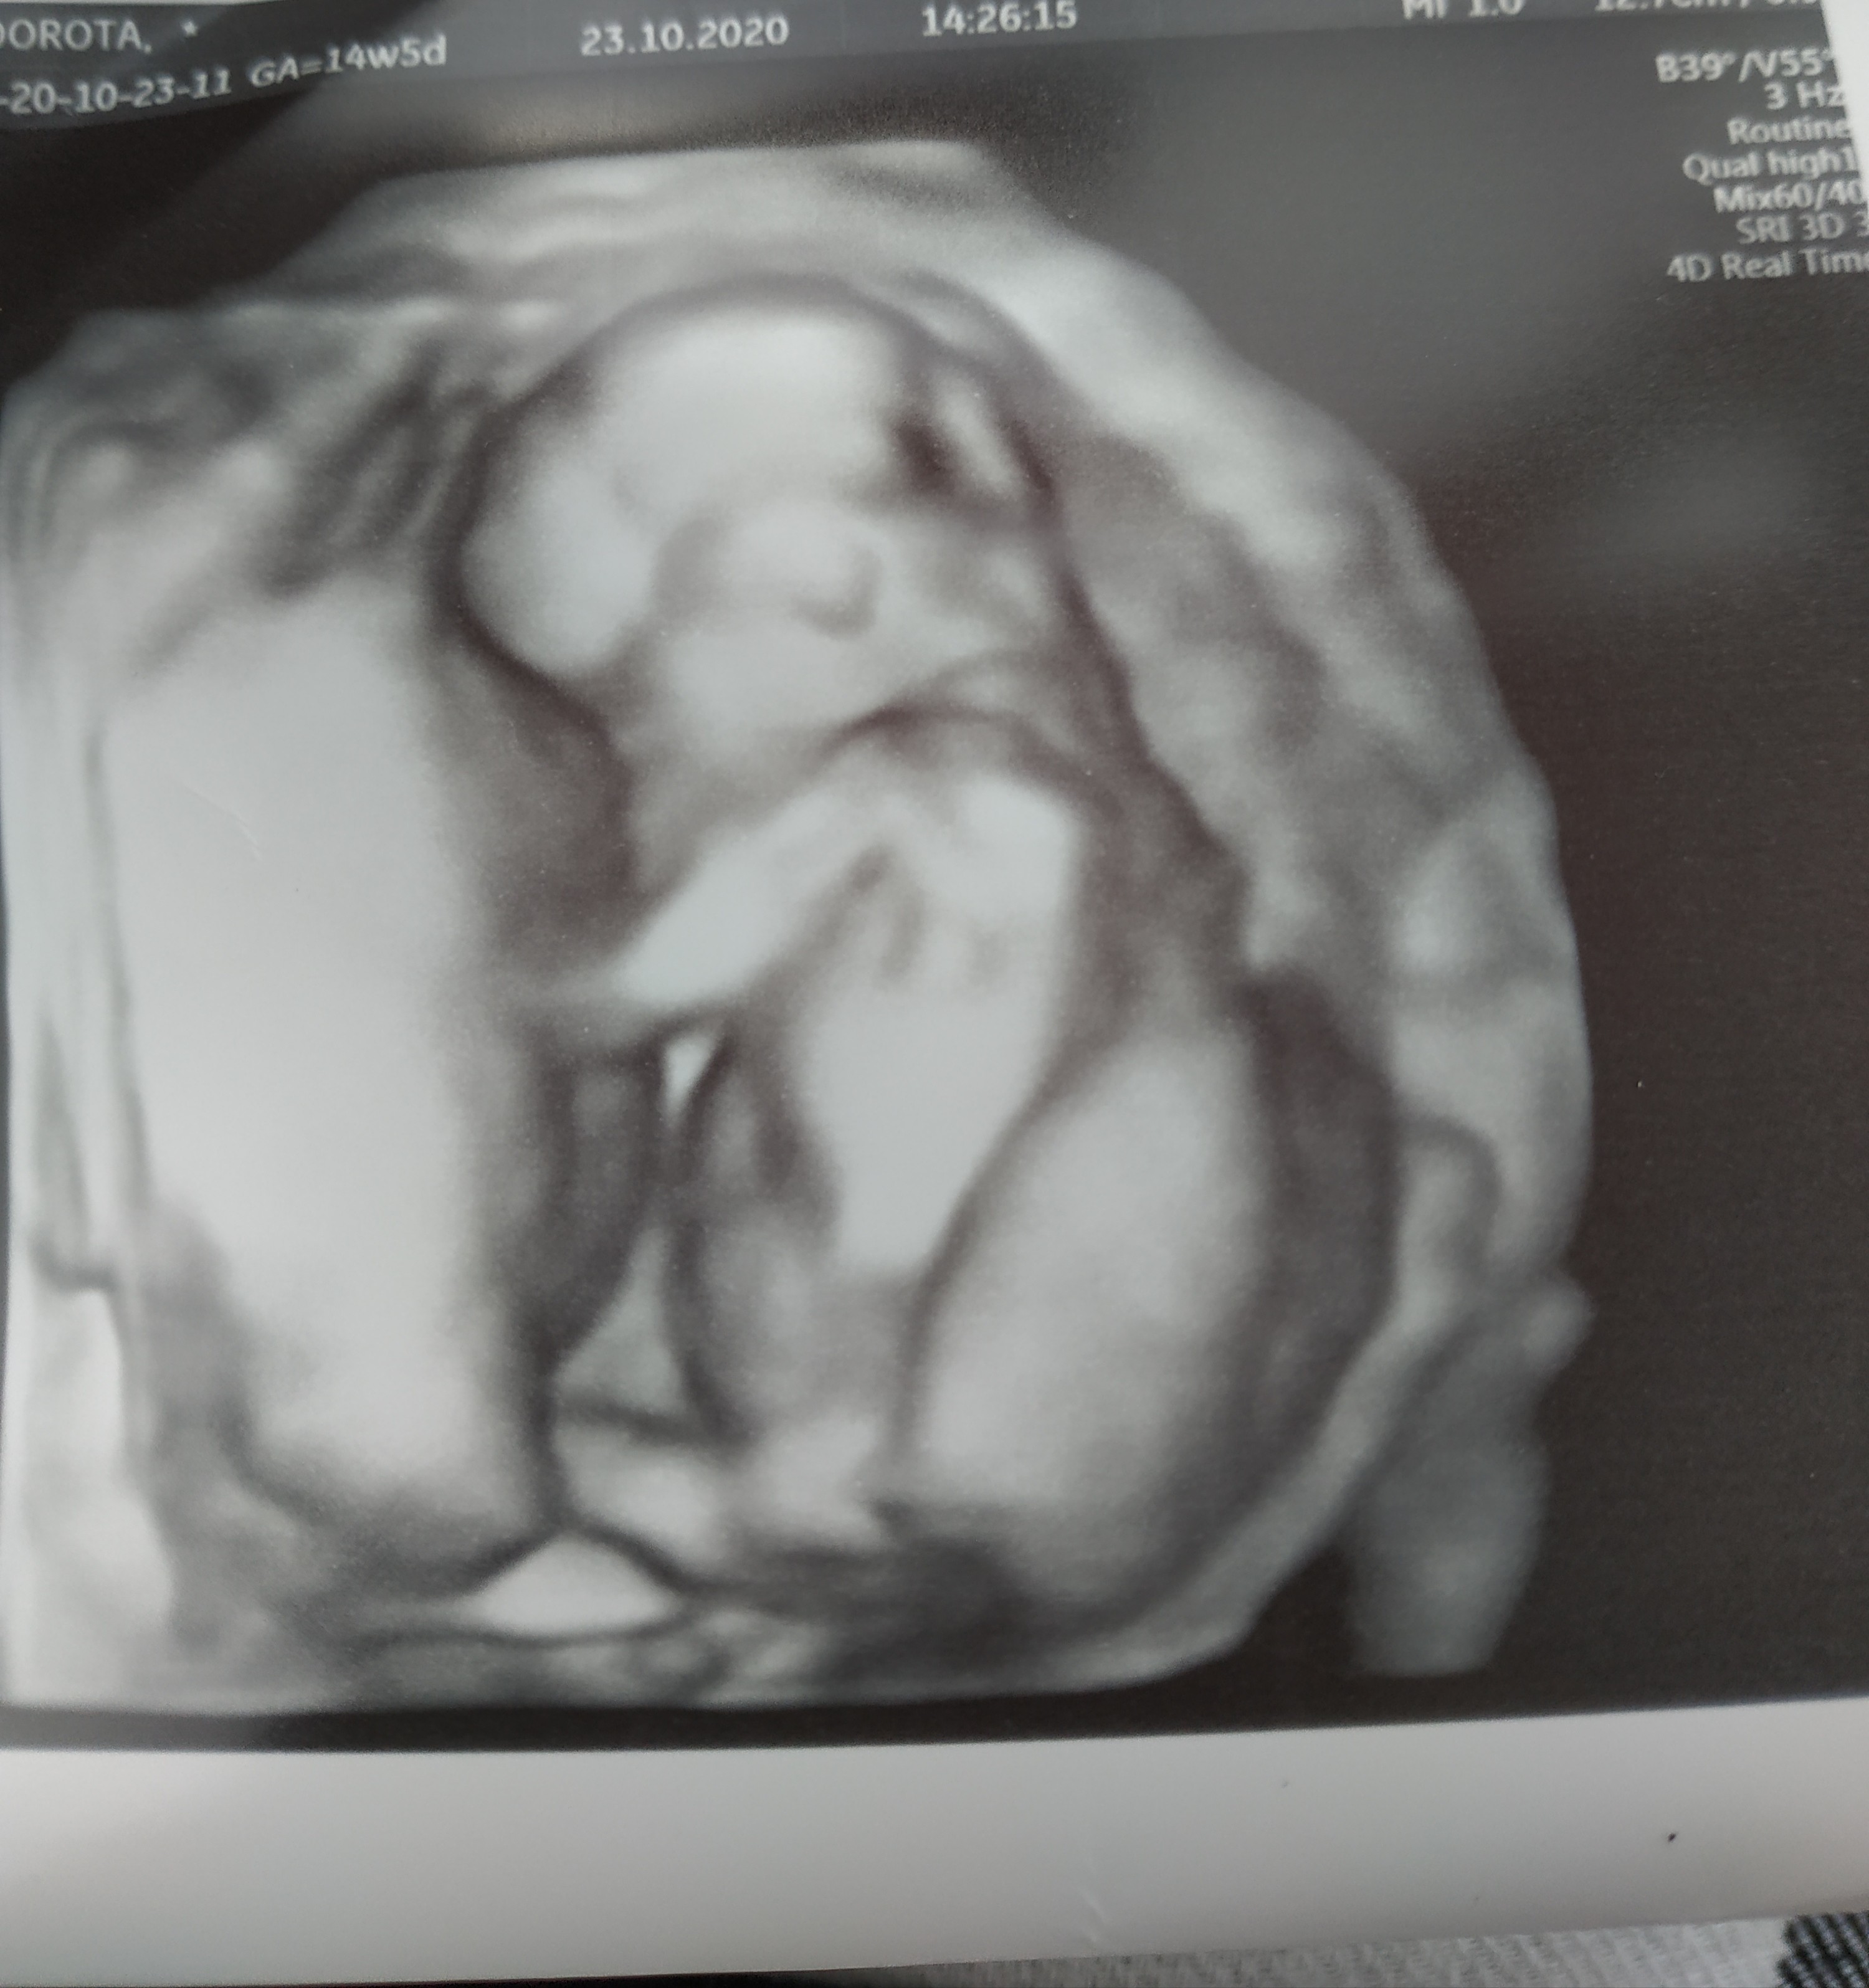

My już po wizycie ♥ pierwsze co udało się zobaczyć przy USG dowcipnym to ptaszka 😂 także będziemy mieć chłopczyka ♥

Maluch rośnie jak na drożdżach, według OM 14+5, według dzisiejszego USG 15+3 i 123 g ♥

Jedyne co mnie niepokoi to dalej wysokie tętno bo 170. Ale Pan dr mówił, że w tym tygodniu dalej jest w normie. Zobacz załącznik 1191740